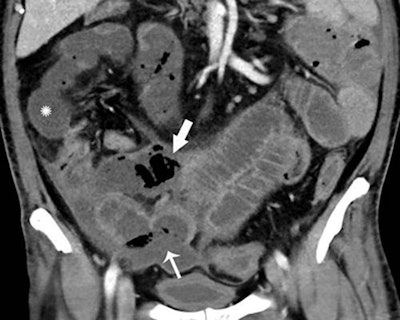

Of these patients, 31% of the CT scans -- representing 3.2% of all patients -- showed bowel abnormalities. These bowel abnormalities, which included thickening and findings of ischemia such as pneumatosis and portal venous gas, were more frequently experienced in intensive care unit (ICU) inpatients, according to the researchers. Surgical correlation in four patients revealed unusual discoloration of bowel in three of the patients and bowel infarction in two patients.

In two of the patients who had bowel resection, pathology results showed ischemia with patchy necrosis. Both of the patients had fibrin thrombi in submucosal arteries, suggesting that the bowel ischemia was caused by these thrombi, according to the researchers.

"Some findings were typical of bowel ischemia, or dying bowel, and in those who had surgery we saw small vessel clots beside areas of dead bowel," Bhayana said in a statement from the RSNA. "Patients in the ICU can have bowel ischemia for other reasons, but we know COVID-19 can lead to clotting and small vessel injury, so bowel might also be affected by this."

The spectrum of bowel findings in these COVID-19 patients could possibly be explained by direct viral infection, small vessel thrombosis, or nonocclusive mesenteric ischemia, according to the authors.